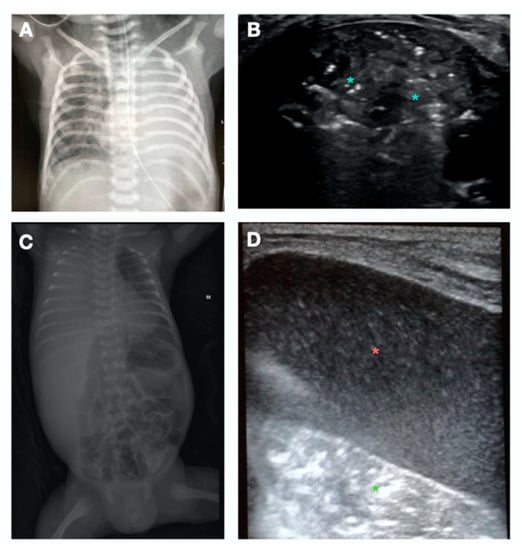

- A-Pattern (Figure 2A), normally aerated lung (aeration score = 0): A-lines, bilateral lung sliding (Video S2). The A-pattern in the absence of lung sliding suggests the presence of pneumothorax. In that case the lung point needs to be searched for. The lung point is point where the pneumothorax ends and the normal contact between the parietal and visceral pleura is restored. The corresponding ultrasound image is a scan where the a normal sliding is detected right aside a static pleura, representing the loss of contact between the parietal and visceral pleura. Therefore after the lung point, the pleural space is filled with air and the pleural sliding is absent (Video S3);

- C-Pattern (Figure 2E): complete loss of aeration (aeration score = 3) leading to lung consolidation. The C-pattern is the only LUS pattern based on the anatomical visualization of the lung. Lung collapse or consolidation remove the A-line artifacts and allow for direct visualization of the lung parenchyma. Lung consolidations (that can highly vary in size and number), generally appear as hypoechoic or “liver-like texture” images, with irregular margins, containing air bronchogram and a vascular pattern enhancing an intraparenchymal pulmonary shunt. Lung consolidation may be due to lung atelectasis, pneumonia or MAS (Figure S5).